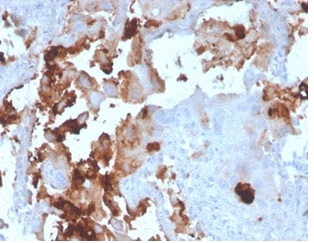

Formalin-fixed, paraffin-embedded human breast carcinoma stained with L-PLUNC Mouse Monoclonal Antibody (LPLUNC1/3206). HIER: Tris/EDTA, pH9.0, 45min. 2°C: HRP-polymer, 30min. DAB, 5min.